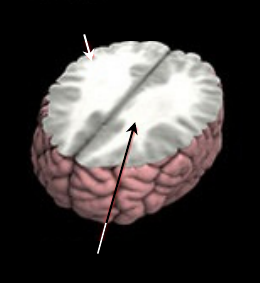

Autism is a neurodevelopmental disorder

characterized by marked deficits in communication,

social interaction, and interests. Various studies of

autism have suggested abnormalities in several brain

regions, with an increasing agreement on the

abnormal anatomy of the white matter (WM) and the

unused brain cells, called gray matter (GM).

(Rachid, et al., 2007), (Fisher, 2011). The WM

connections between brain regions are important for

language and social skills. Normally, as children

grow into teenagers, in order to understand and

respond to the world, the brain undergoes 2 major

changes — the creation of new connections in WM,

and the elimination, or “pruning,” of GM. Figure 1

shows the region of WM and GM. The brain-

imaging scan called a T1-weighted MRI (Magnetic

Resonance Imaging), which can map structural

changes during brain development (Fisher, 2011).

Figure 1: The connections between WM and GM.

Gray Matter

White Matter